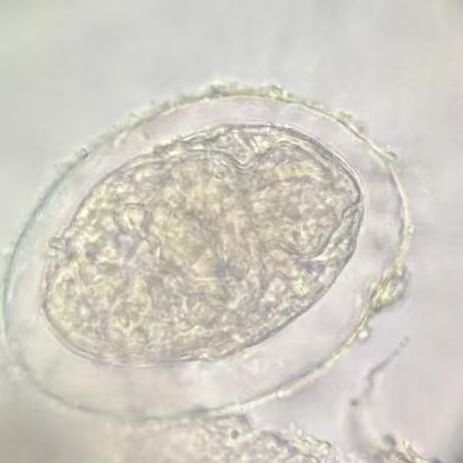

二等奖

第七组

黄斯妤 徐慧茹 王紫诺 马丽琪